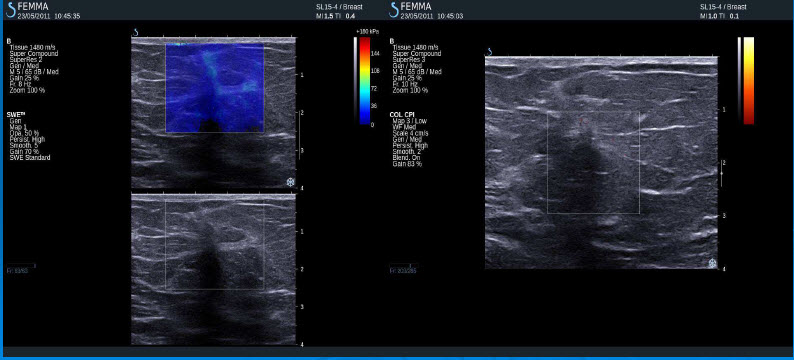

Negativní výsledky elastografie / histologicky potvrzená malignita

Mucinozní adenokarcinom

DCIS

Nízce diferencovaný duktální karcinom

Lobulární karcinom

Duktální invazivní karcinom